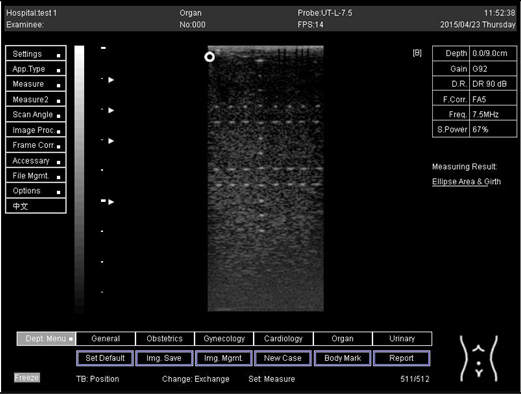

Depth (cm)Diagram

5.0 The horizontal distance cannot be measured for the image of this depth

6.0 The horizontal distance cannot be measured for the image of this depth

7.0 Biomimetics 07 00130 i035